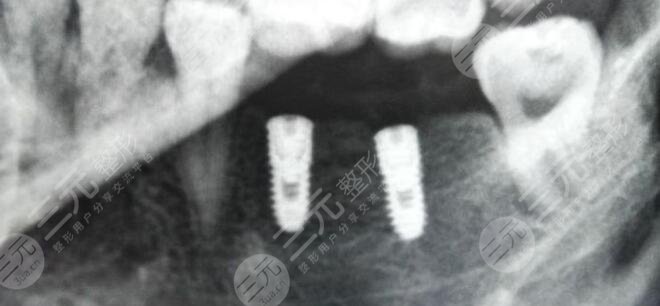

牙齒雖然說是人體很堅(jiān)固的部位之一,但如果在日常生活當(dāng)中不注重牙齒清潔和護(hù)理的話,也會導(dǎo)致牙齒出現(xiàn)各種各樣的問題,從而影響到一個(gè)人的咀嚼功能,因此就需要通過修復(fù)技術(shù)來進(jìn)行修復(fù)。牙齒種植是一種理想的牙齒修復(fù)方式,通過此項(xiàng)技術(shù)能夠很好的改良牙齒缺失問題,使牙齒外觀和咀嚼功能恢復(fù)到與真牙接近的狀態(tài),因此受到了很多愛美女性的信任和追捧。

而牙齒種植體也是大眾一直都很關(guān)注的熱點(diǎn),不同的種植體在價(jià)格、優(yōu)勢以及缺點(diǎn)方面都是存在一定不同的,下面就針對牙齒種植體十大排名來為大家進(jìn)行一個(gè)簡單的盤點(diǎn),大家可以大概的了解一下,并從中選擇出自己理想的牙齒種植體材料。

一、牙齒種植體十大排名